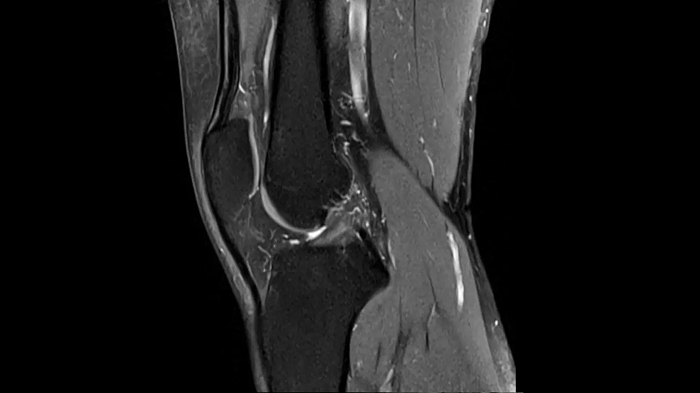

PD TSE Fat Sat with Deep Resolve and Simultaneous Multi-Slice

For clear imaging of the knee, outstanding fat suppression and performance are possible. Integrating the influence of Deep Resolve with the established Simultaneous Multi-Slice technique.

SMS 2 | Deep Resolve Gain & Sharp

0.4 x 0.4 x 3.0 mm2

TA 2:56 minutes

MAC-ID: 7aaaa0198. Image Credit: Siemens Healthineers